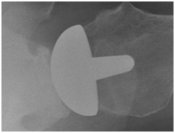

Arthritis of the shoulder shoulder arthritis

X-ray of shoulder demonstrating the arthritis of shoulder